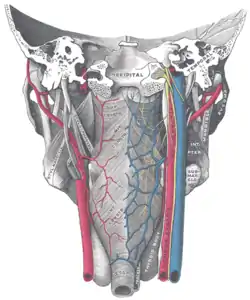

Muscles of the pharynx, viewed from behind, together with the associated vessels and nerves | |

They are innervated by the pharyngeal branch of the vagus nerve (CN X) with the exception of the stylopharyngeus muscle which is innervated by the glossopharyngeal nerve (CN IX).[1]

They are primarily supplied by branches of the facial artery. Other blood supply includes the ascending pharyngeal artery, lingual artery, and ascending and descending palatine arteries.